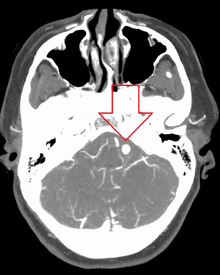

Diagnosis of a ruptured cerebral aneurysm is commonly made by finding signs of subarachnoid hemorrhage on a computed tomography (CT) scan. If the CT scan is negative but a ruptured aneurysm is still suspected based on clinical findings, a lumbar puncture can be performed to detect blood in the cerebrospinal fluid. Computed tomography angiography (CTA) is an alternative to traditional angiography and can be performed without the need for arterial catheterization. This test combines a regular CT scan with a contrast dye injected into a vein. Once the dye is injected into a vein, it travels to the cerebral arteries, and images are created using a CT scan. These images show exactly how blood flows into the brain arteries.